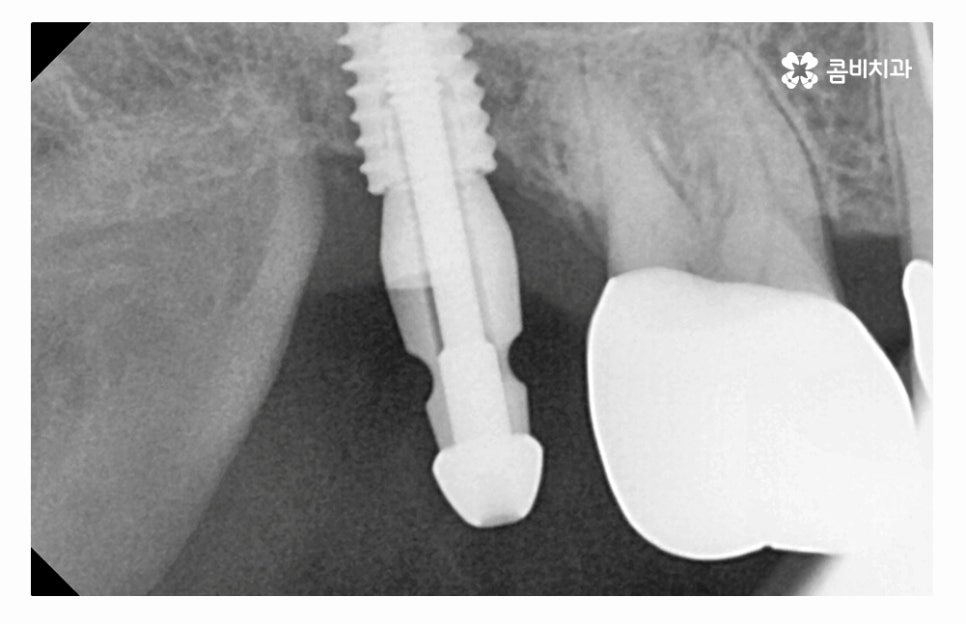

임플란트수술의 원리는 잇몸 뼈에 인공 치근을 식립하고

지대주로 단단하게 고정력을 얻은 후에 보철물을 연결하여

치료를 마무리하게 되는데 자연치아도 그렇듯이

임플란트 역시도 잇몸 뼈의 상태가 매우 중요하다고 할 수 있는데요.

치아를 잃게 되었을 때 곧바로 임플란트 수술을 해야 하는 이유도

임플란트를 건강하게 치료하기 위해서는 잇몸 상태가 중요한데

치아를 잃고 그대로 방치하면 잇몸이 점점 흡수되기 때문이라고 할 수 있어요.